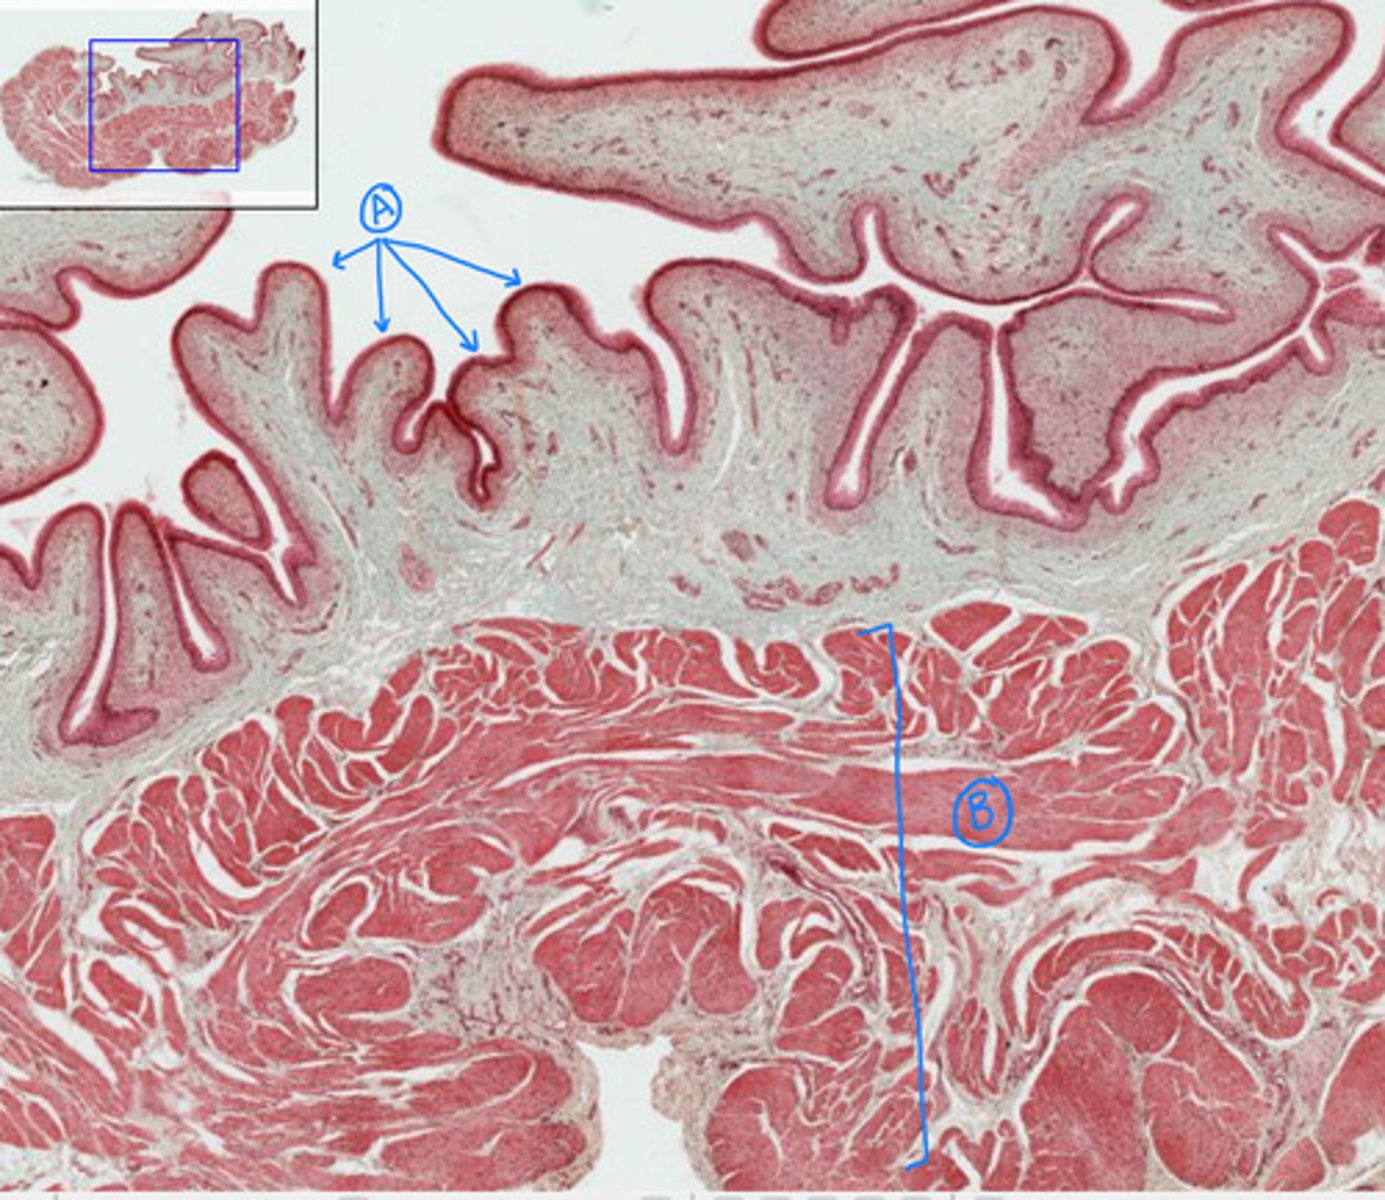

villi of small intestine

A

simple columnar epithelium

B

outer longitudinal layer of the small intestine

C

muscularis layer of the small intestine

E

inner circular later of the small intestine

D